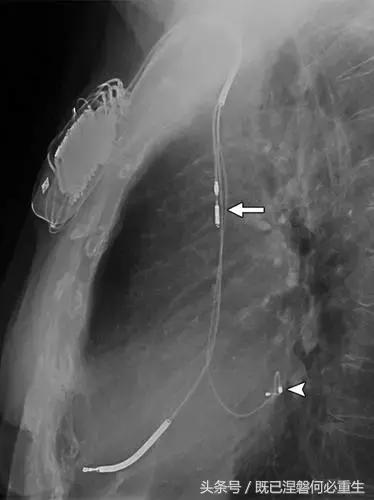

图。 6B 75岁的男性患有心房导线脱位。

B,Medtronic双腔起搏器的右心房导联(箭头)在正面(A)和侧面(B)图像上显示纯垂直路线。 铅在心房中自由浮动。 患者抱怨经常心悸,并且设备检查显示不能可靠地去极化心房。 心房导线修订(未示出)导致心悸消除。 心房导线的推荐放置位于右心耳,但右心房中的导联可充分发挥作用。 在任一位置正确固定到壁上的引线通常将显示一定程度的曲率。